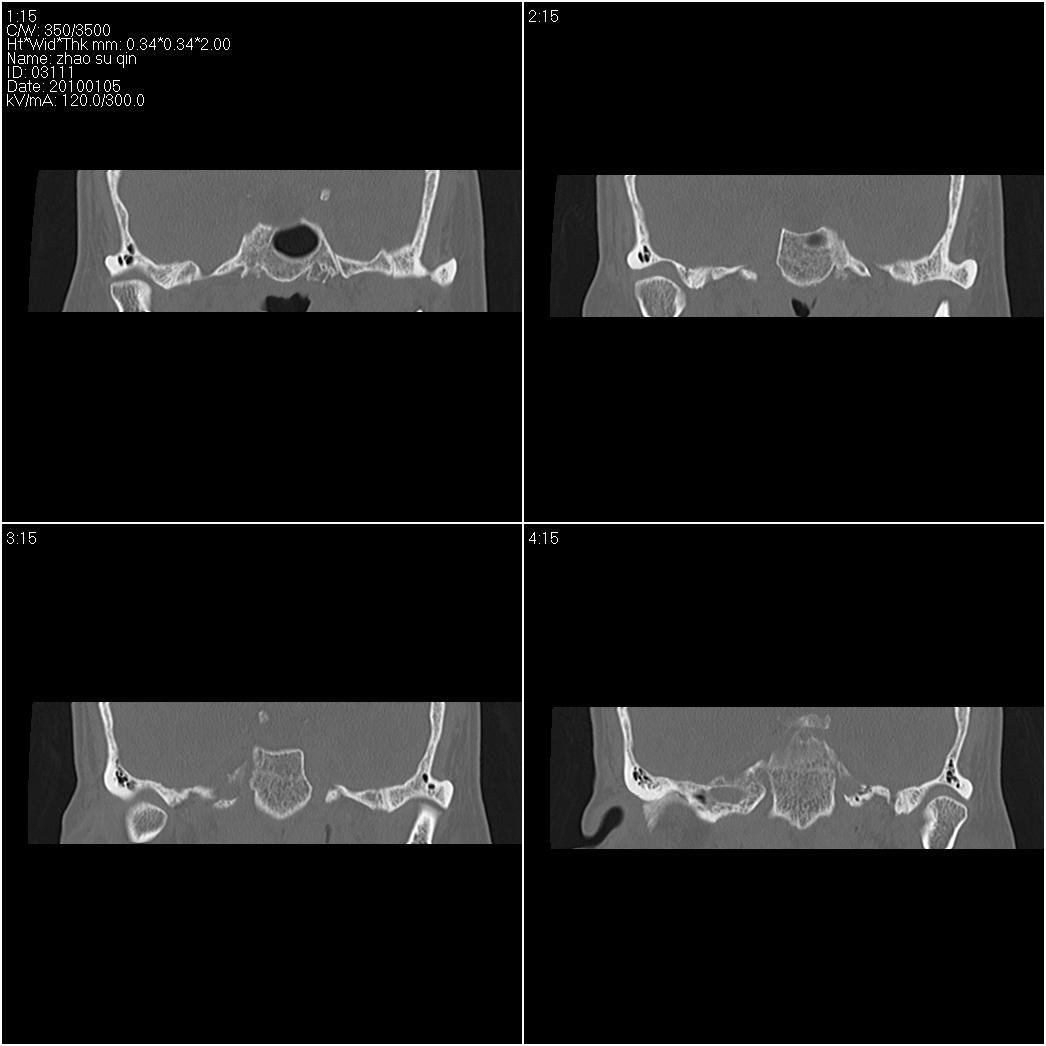

标题: CT24015:一个头部外伤患者进行鉴定,除了左侧筛板骨折,哪 [打印本页]

标题: CT24015:一个头部外伤患者进行鉴定,除了左侧筛板骨折,哪

1)左侧筛板骨折。2)双侧筛窦炎症(或积血)。